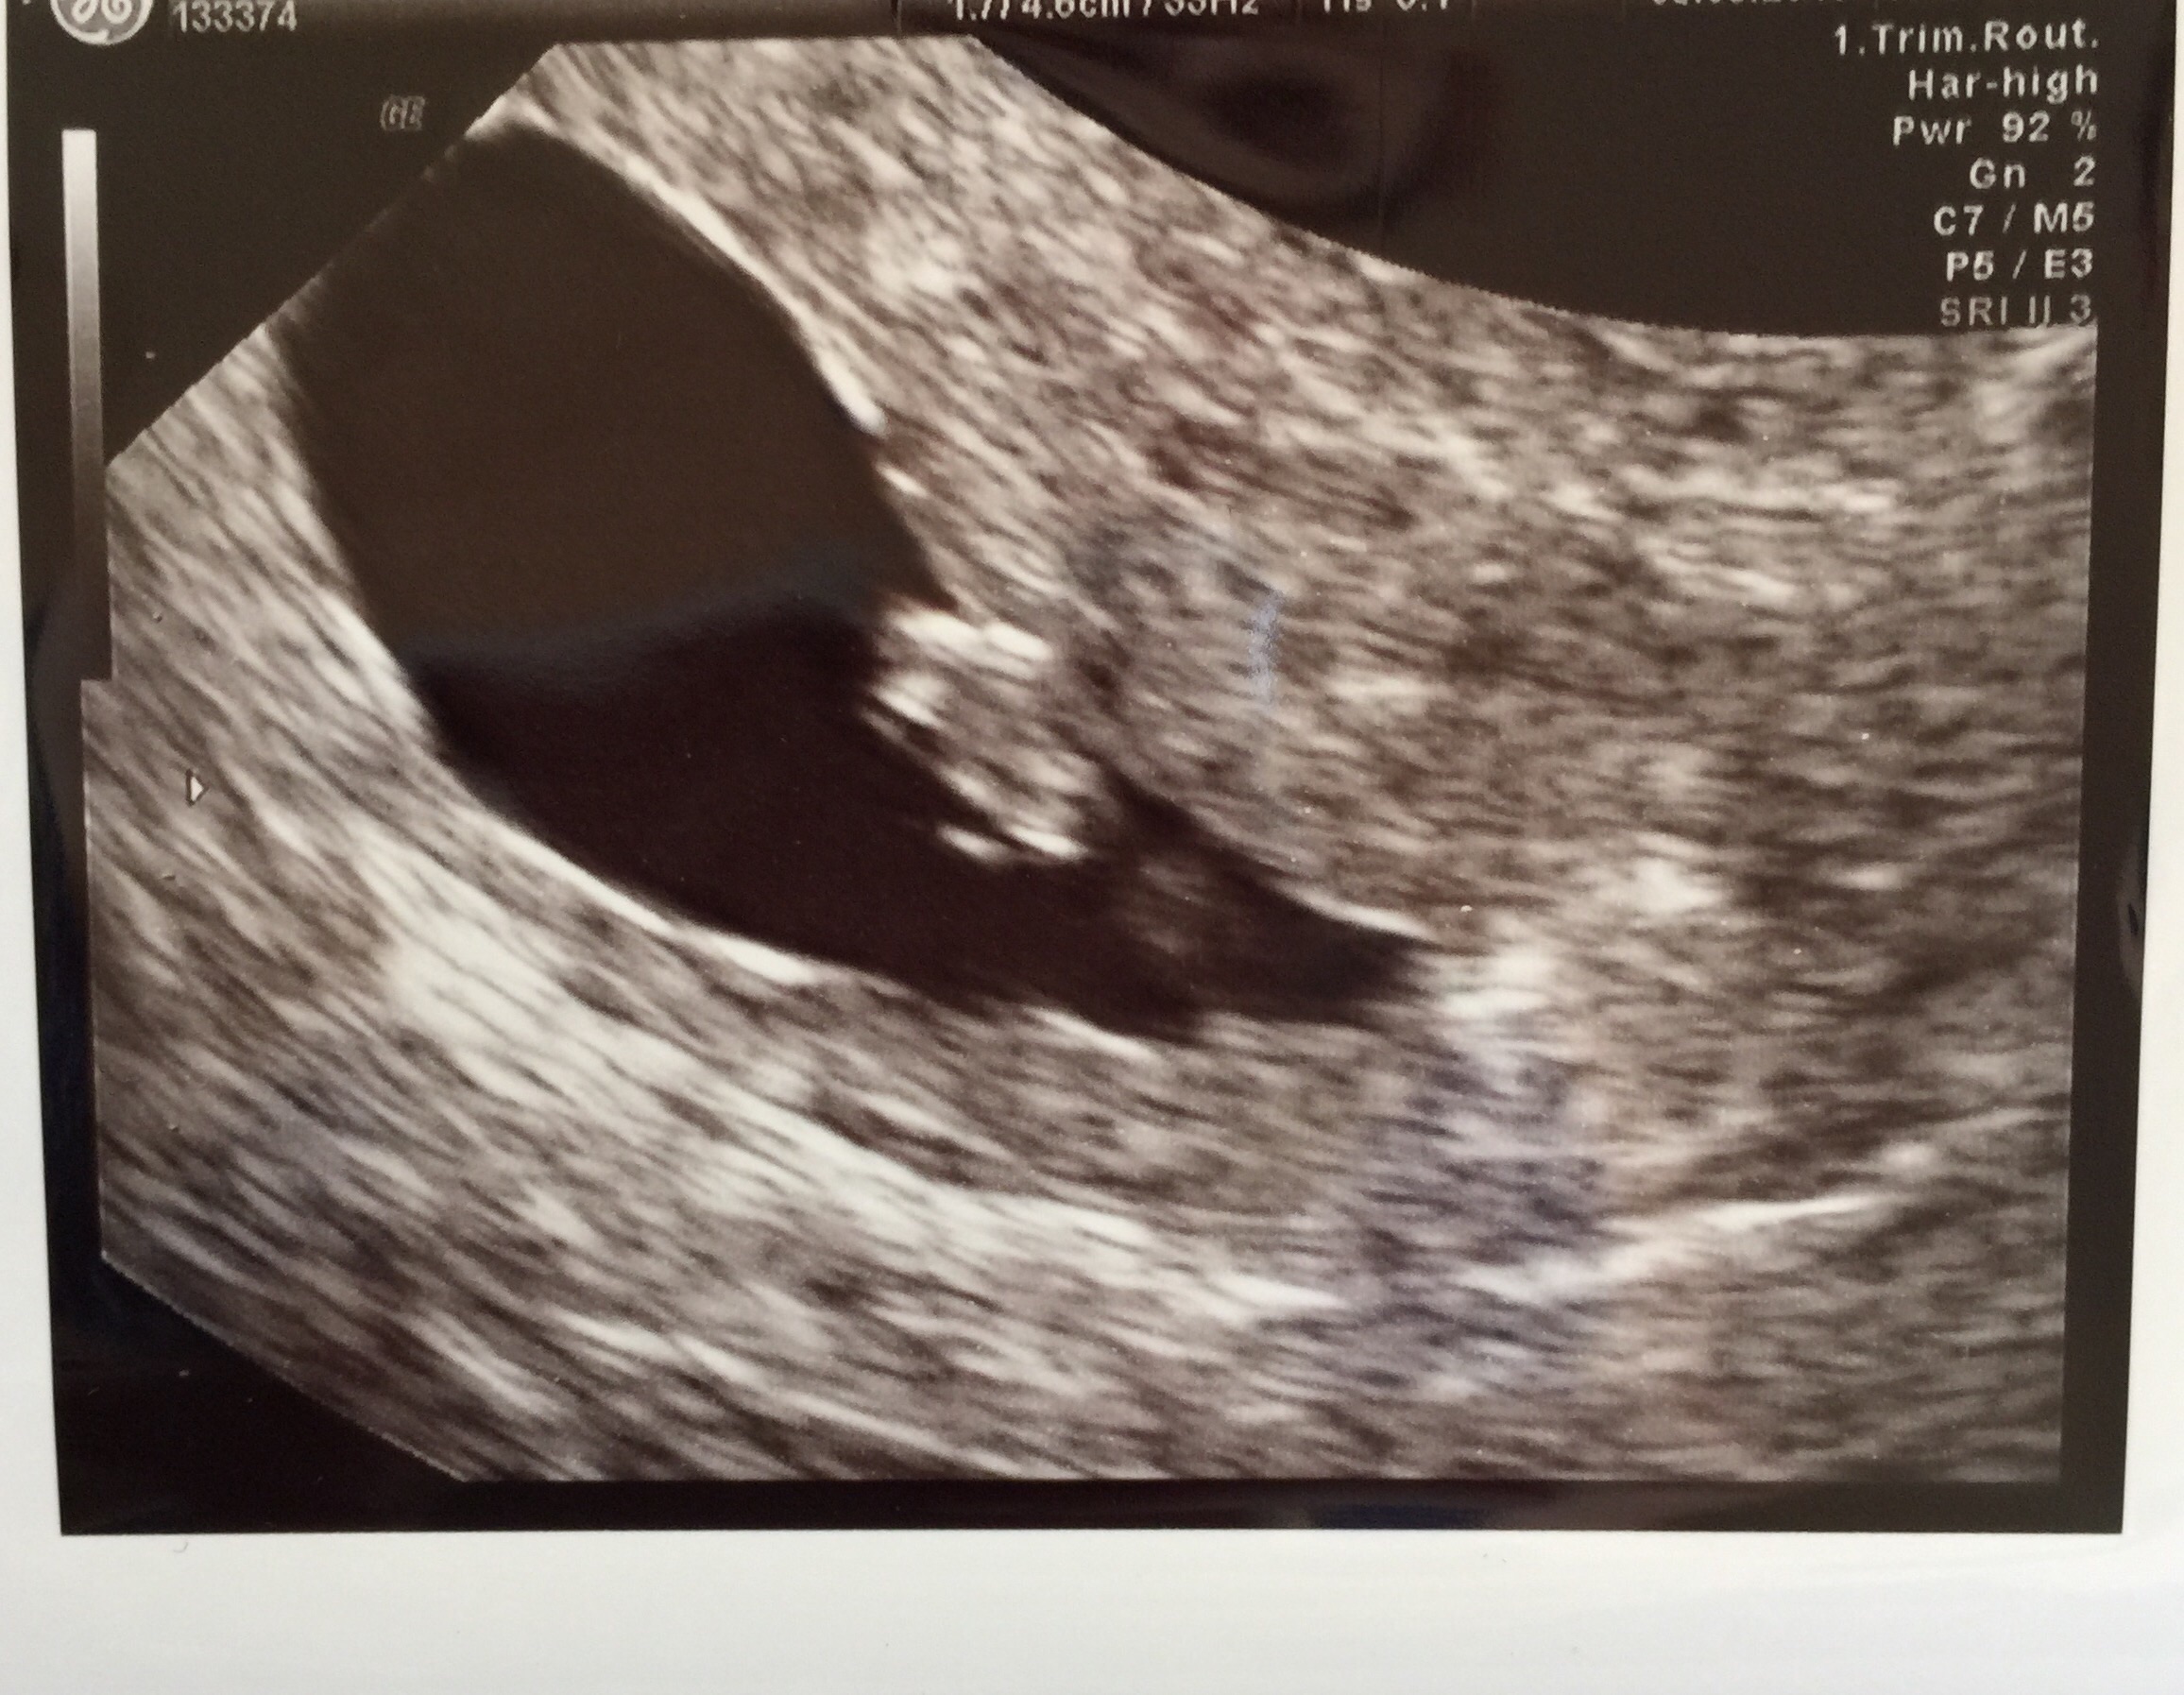

• I'm 10 weeks today. My due date is April 7th. This picture is actually from my second ultrasound that I got yesterday. I got my first one done at 7 weeks and 5 days due to some minor bleeding which they determined was from a small blood blister in my uterus. As of yesterday we got the good news that the blood blister has shrunk dramatically! So now my appointments will continue on as normal. The baby's heartbeat was 156 at my first appointment and yesterday it was 175. I'm not sure I can accurately describe how happy I was to see my little baby moving around on the screen yesterday! It's truly something magical.